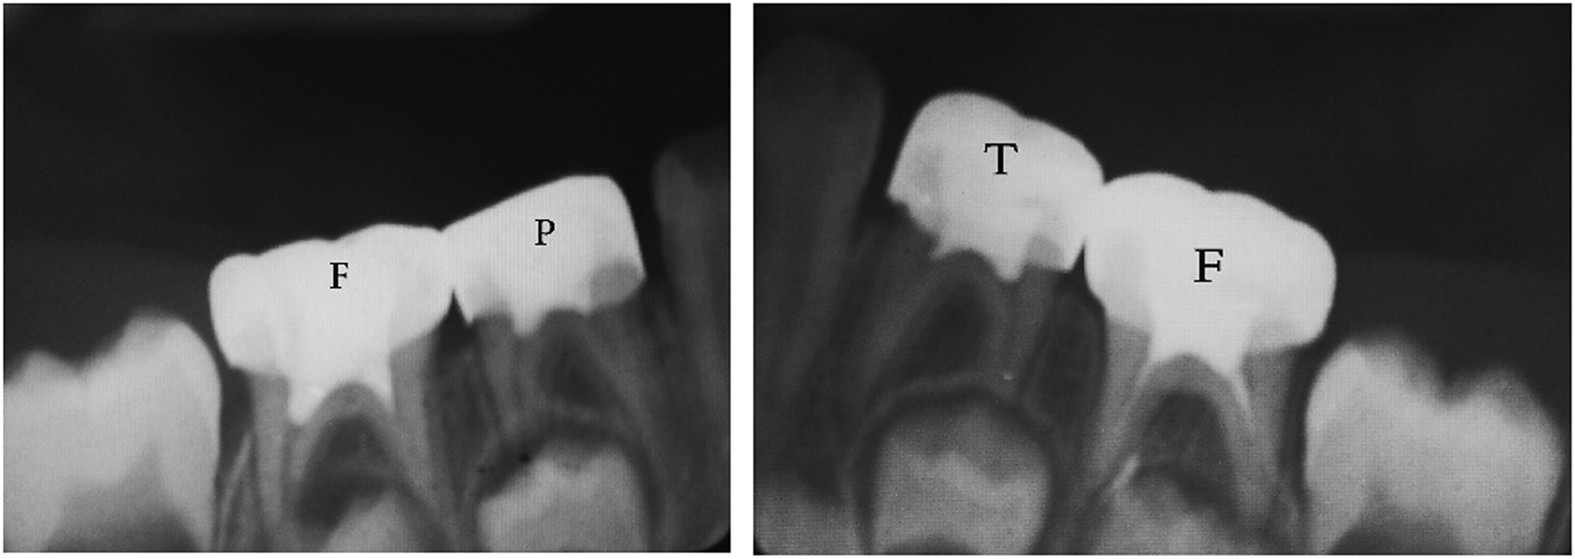

From: Clinical and radiographical evaluation of propolis and thymus vulgaris extracts compared with formocresol pulpotomy in human primary molars

Six months post operative.